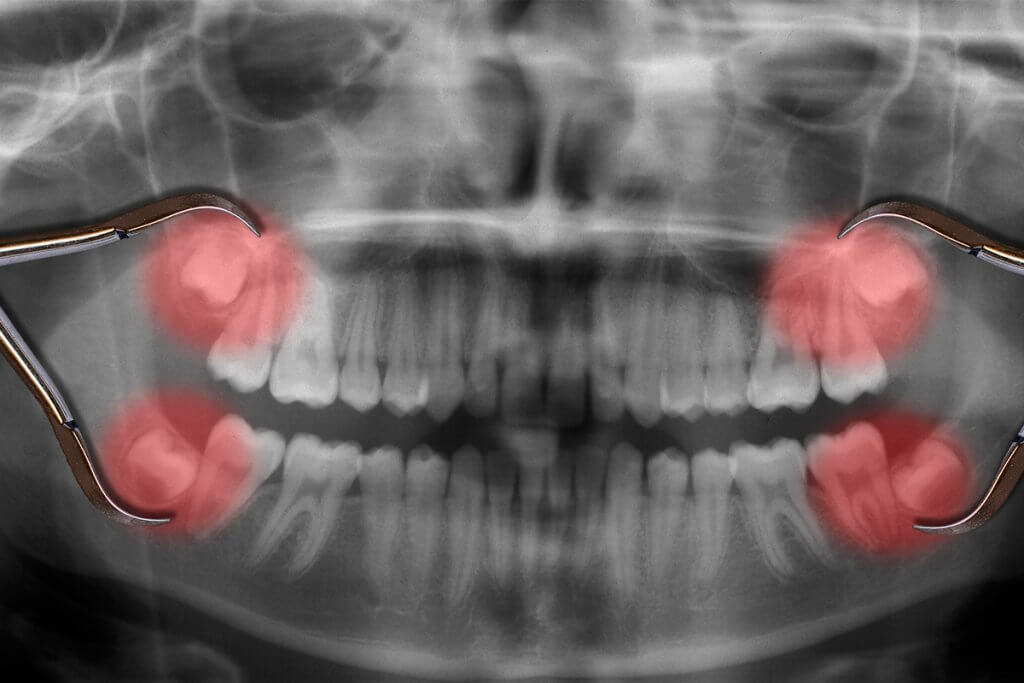

Panoramic dental Xray, fully impacted wisdom tooth is seen Stock Photo Alamy What Is A Fully Impacted Wisdom Tooth There are four different kinds of impactions, some of. Partially impacted wisdom teeth — parts of teeth. an impaction is when one of these third molars (wisdom teeth) does not erupt properly. this is known as a fully impacted wisdom tooth. impacted wisdom teeth are classified by the direction and depth of impaction, the amount of available. What Is A Fully Impacted Wisdom Tooth.

impacted wisdom teeth happen when your third molars become partially or fully trapped in your gums or jawbone. Generally, wisdom teeth become impacted. There are four different kinds of impactions, some of. fully impacted wisdom teeth — teeth are trapped entirely under the gums and are not visible. an impaction is when one of these third molars (wisdom teeth) does not erupt properly. impacted wisdom teeth are classified by the direction and depth of impaction, the amount of available space for tooth eruption, and. This can lead to a number of. Partially impacted wisdom teeth — parts of teeth. impacted wisdom teeth that cause pain or other dental problems usually are taken out with surgery, also known as. this is known as a fully impacted wisdom tooth.